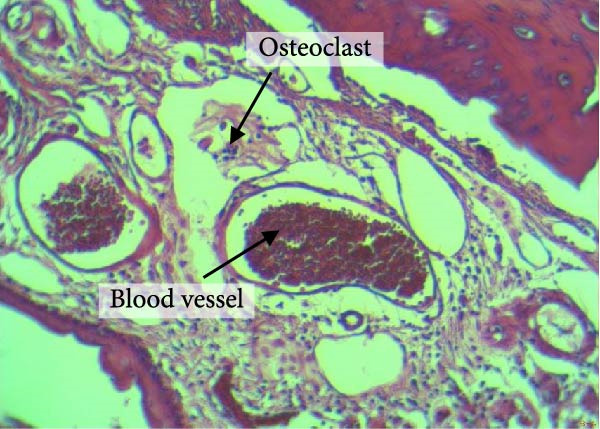

Figure 4 shows the periodontal tissue light‐microscopic findings in the study groups. As shown, the number of blood vessels, osteoclasts, and Howship’s lacunae was significantly higher in rats subjected to stress and CE injection for a 40‐day period, compared with others.

Figure 4H&E staining. Blood vessels and osteoclasts in different subgroups: (A) orthodontic treatment/CE injection/stress (chronic); (B) orthodontic treatment/CE injection/stress (acute); (C) no orthodontic treatment/CE injection/stress (chronic); (D) no orthodontic treatment/CE injection/stress (acute).(A)(B)(C)(D)